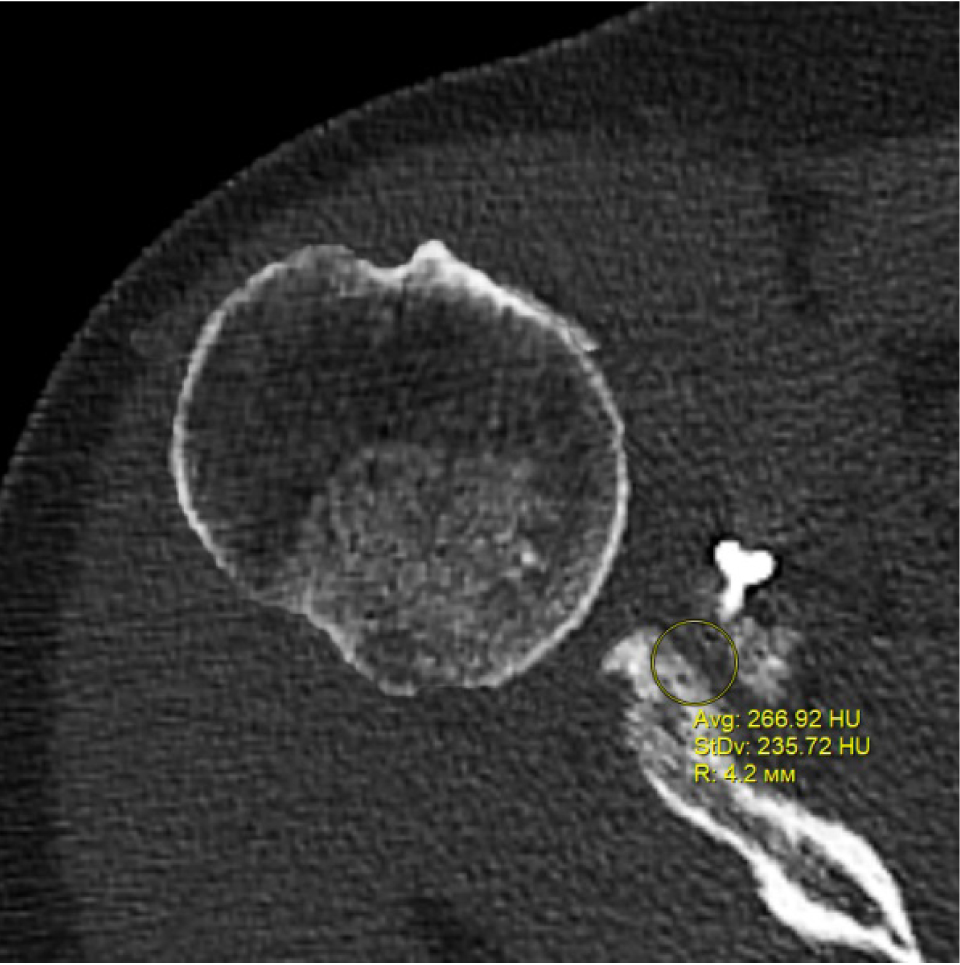

В программном обеспечении, на аксиальных КТ срезах оперированного плечевого сустава, выбирали инструмент «круг», который позволял посчитать среднюю плотность тканей внутри круга в единицах Хаунсфильда. Шкала единиц Хаунс-филда (HU) – шкалалинейного ослабления излучения по отношению к дистиллированной воде, рентгеновская плотность которой была принята за 0 HU (при стандартных давлении и температуре). Круг устанавливали таким образом, чтобы одна его половина была заполнена тканью гленоида, вторая половина тканью трансплантата (рис. 1–3). Оценивали плотность тканей над проксимальным винтом, между винтами, под дистальным винтом. Полученные данные анализировали с помощью пакета Microsoft Excel.

Рис. 1. Оценка плотности ткани под дистальным винтом

Через 3 месяца после оперативного лечения по данным анализа КТ срезов были получены следующие результаты: плотность ткани над проксимальным винтом составили (424 ± 24,3) HU, между винтами (460 ± 23,4) HU, под дистальным винтом (587 ± 49,1) HU. Спустя 6 месяцев после операции плотность ткани над проксимальным винтом составили (320 ± 28,7) HU, между винтами (424 ± 36,2) HU, под дистальным винтом (623 ± 33,4) HU. Через 12 месяцев после операции показатели были следующие над проксимальным винтом (276 ± 22,1) HU, между винтами (387 ± 31,1) HU, под дистальным винтом (662 ± 43,2) HU (таблица).